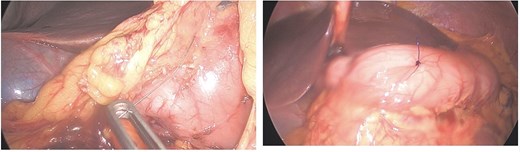

Initial laboratory parameters were unremarkable. Abdominal computed tomography (CT) (03.05.2024) revealed a linear, hyperdense foreign body (Fig. 1)—consistent with a metallic wire—penetrating the anterior gastric wall and abutting the dorsal rectus sheath left paramedian [10]. Minimal free fluid was noted, but no pneumoperitoneum. Two small hepatic lesions were incidentally noted, suggestive of hemangiomas.

Abdominal CT (03.05.2024), hyperdense foreign body (metallic wire).